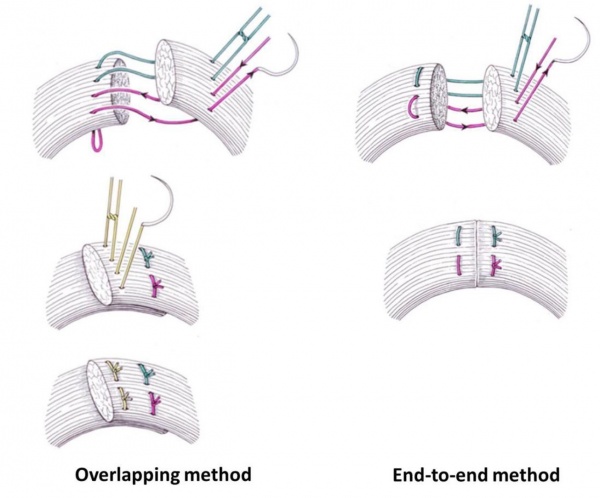

- קרעים של הסוגר החיצוני ניתן לתקן בשתי שיטות: End to end ו- Overlap

- קרע דרגה 3a (עד 50% מעובי הסוגר החיצון) רצוי לתקן בשיטת end-to-end בתפרי 0–3 WPDS בתפרי 0–2 (Vicryl (polyglactin

- קרע דרגה 3b (מעל 50% מעובי הסוגר החיצון) רצוי לתקן באם הקרע חלקי בשיטת end-to end, ואילו אם הקרע שלם שתי הגישות קבילות באותה המידה